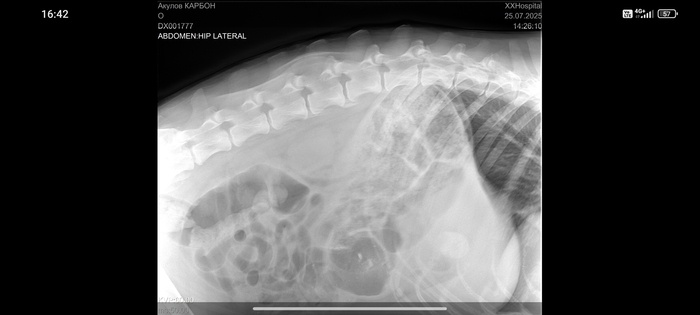

Сделали рентген и анализ крови.

Заключение - проблемы в позвоночнике.